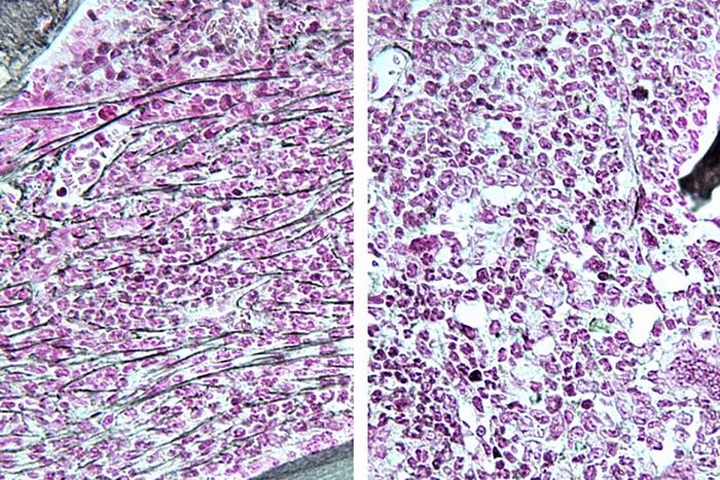

Los estudios -ambos realizados en muestras de pacientes y modelos animales- descubrieron que la inhibición de una proteína llamada RSK1 reduce la inflamación y detiene la progresión de los cánceres de la sangre llamados neoplasias mieloproliferativas (NMP), así como de una forma agresiva de leucemia mieloide aguda (LMA). Con el inhibidor de RSK1 ya en fase de pruebas clínicas, es probable que se acelere su uso como tratamiento de los cánceres hematológicos.

En el estudio de 'Nature Communications', la inhibición de RSK1 ayudó a invertir la progresión de los NMP en ratones, reduciendo la fibrosis, o formación de cicatrices, en la médula ósea. La inhibición de RSK1 eliminó hasta el 96 por ciento del cáncer en ratones al cabo de cuatro semanas. También se demostró que impedía que la enfermedad crónica se transformara en LMA secundaria.